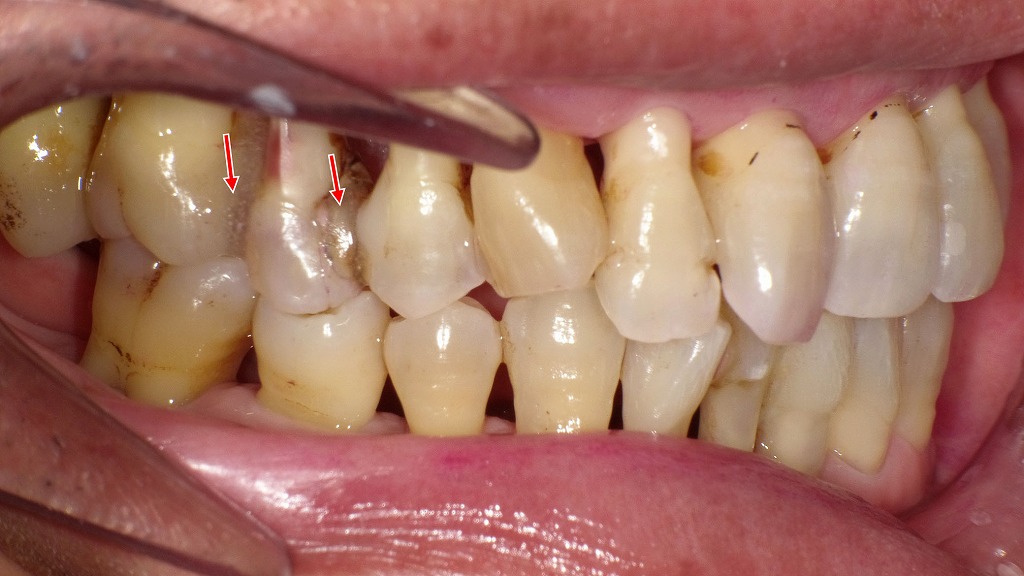

👀右側面観・左側面観

重度歯周病治療後の側面所見です。上顎臼歯部には歯の動揺を抑える目的で暫間固定(T-FIX)を行っています。歯周治療により炎症が改善し、歯ぐきの腫れが引いた結果、特に上顎臼歯部で歯肉退縮と歯根面の露出が明瞭に認められます。現在はプラークコントロールが良好で、定期的なクリーニングにより歯周組織は安定した状態を維持しています。